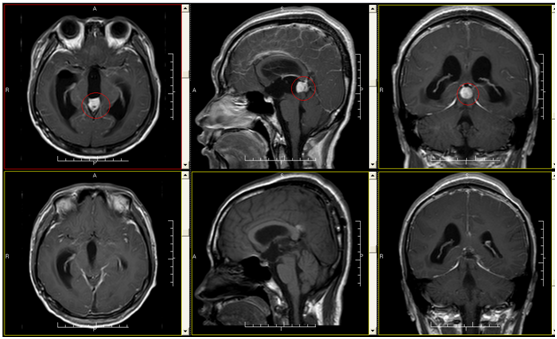

21岁,青葱的岁月,正是意气风发,朝气蓬勃的年龄,可在大学生小方身上,我们看到的更多的是人生的酸苦。2016年3月的一天,持续头痛和全身抽搐发作,突然闯进了这个小伙子的美好生活。发病后家人送小方到当地医院就诊,头颅MR提示:“1.松果体区占位性病变,拟为肿瘤性病变,生殖细胞瘤?松果体细胞瘤?2.梗阻性脑积水;3.可疑乙状窦及横窦血栓形成”。为求进一步治疗,来我院就诊。入院考虑“松果体区占位性病变,梗阻性脑积水,症状性癫痫”,完善术前准备后予行手术切除肿瘤,术后症状缓解,癫痫无发作。

松果体区肿瘤的手术治疗目前仍是神经外科的一大挑战。该区域位置深在,毗邻重要血管神经,特别是大脑深部静脉对手术入路起着明显的阻碍作用,而损伤静脉往往会导致术后严重的并发症及术后反应,导致手术失败。目前Poppen 入路是处理松果体区肿瘤最为常用的手术入路。